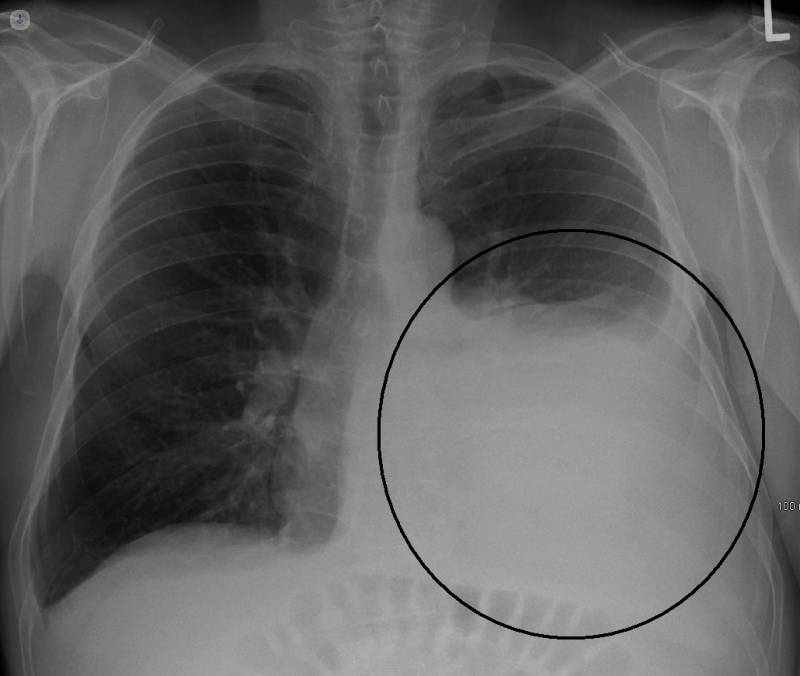

La incidencia de cánceres de pleura en Cerdanyola del Vallés es la más alta en todo el Estado —al menos hasta el 2018, puesto que la recopilación de datos se paró en seco por falta de recursos—. Cáncer de laringe, de pulmón, asbestosis, derrames pleurales, carcinomas gastrointestinales. Mesotelioma pleural, un cáncer muy virulento que solo se puede desarrollar por un motivo: la exposición al amianto. La esperanza de vida desde el diagnóstico suele ser de quince meses, pero oscila entre el año o dos años.

Son cuarenta años los que puede tardar el polvo asesino en despertar de su letargo. ¿Qué pasa si la presión en el pecho abruma, y cada una de las quince respiraciones por minuto son un suplicio? ¿Si los pulmones se han convertido en bloques de hormigón inamovibles? La tos seca y constante azota el tórax como un martillo perforador que intenta quebrantar el cemento. El asbesto clavado en los pulmones permanece latente hasta que se endurece y se manifiesta en forma de enfermedad en muchos casos, al cabo de mucho tiempo. El mayo del 2021, el Supremo desestimó los recursos que había presentado Uralita y falló en favor de las víctimas, que llevan años en procesos de demandas colectiva. El juez determinó que la empresa expuso a graves riesgos a la población y los trabajadores con conocimiento de que el material era nocivo.

Las enfermedades se dividen en tres bloques, está el primero, que el neumólogo denomina como los del contacto directo: trabajadores productores de placas de fibrocemento, sus familiares, y vecinos de la zona. La segunda fase son los empleados que trabajan con las placas producidas, es decir, mucha gente del sector de la construcción, como podrían ser albañiles.

Por último, tenemos la fase más peligrosa por la dificultad que supone controlarla, la de las placas desgastadas: “hay millones, millones y millones de techos que empezarán, o ya han empezado, a actuar como pequeños focos. Los enfermos por esta última etapa cada vez serán más, ya que, si no se toma en serio el desamiantado en todo el mundo, esos tejados cada vez se harán más viejos y producirán más enfermedad. Hemos pasado del gueto de enfermedad en el pueblo, a universalizar la problemática”, concluye el médico.

Rafaela vivió hasta el 29 de diciembre del 2017. Pasaron poco más de dos años del diagnóstico hasta ese día. “Soy feliz con ver el sol y respirar”, Rafaela solía decir esa frase antes de enfermar. Miguel la cuidaba en casa, al principio incluso podían salir a pasear a la luz de su apreciado sol. Pero llegó un momento en el que su pecho le impedía respirar, y dejó de salir. Se agotaba. Se fue deteriorando. Rafaela era y sigue siendo muchas cosas más que víctima de un genocidio laboral, pero la enfermedad se encargó de hacerle perder la autonomía, el pelo, la masa muscular y el brillo en los ojos. Algo macabro es que la culpa cae en hombros de a quién no le pertenece. En este caso, cayó como una losa en las espaldas de su padre, el peón de Uralita. Murió antes que ella, meses después de saber el diagnóstico de su hija: estaba acostumbrado a acudir a entierros de compañeros, pero el pronóstico de Rafaela le hizo caer en una depresión en la que dejó de comer, hablar y salir de casa. Pese a la muerte de su padre y sus años de intentar recuperarse de una enfermedad terminal probando tratamientos experimentales estadounidenses, Rafaela nunca dejó de creer en la vida.